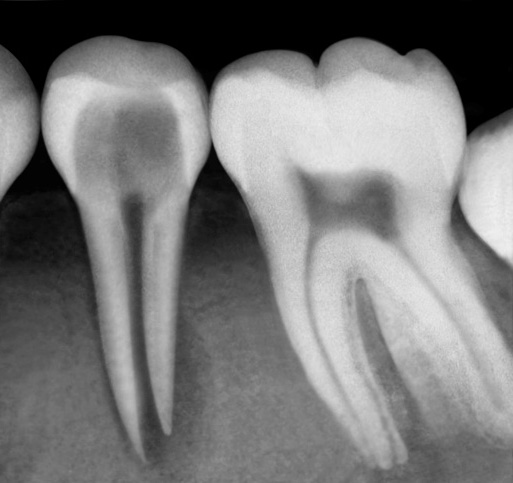

Strategies for endodontic retreatment

Read article